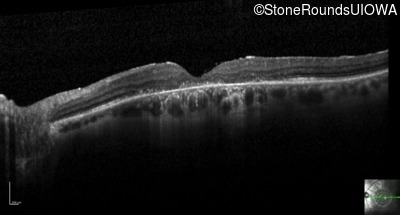

Optical Coherence Tomography - Right - 20/60 sc

Exemplar / OCT Stack